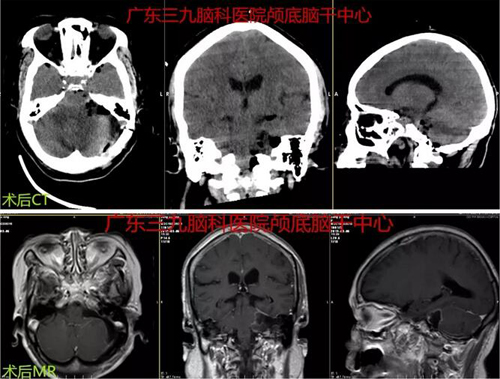

图3:术后CT及MR示左侧桥小脑角区术后改变,原病变已切除。